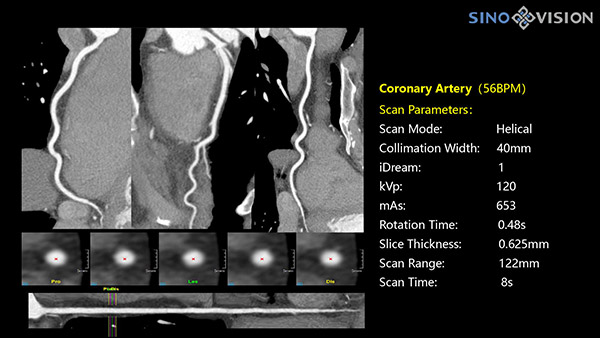

Инновационный 128-срезовый компьютерный томограф SinoVision InsitumCT 568 – это сочетание высокой скорости работы, низкой дозы и максимума возможностей для подавляющего большинства клинических случаев, как в рутинных, так и в углубленных специализированных исследованиях, в том числе педиатрические и кардиологические исследования при сверхнизких дозах.

РМК

Полнофункциональный 128-резовый компьютерный томограф InsitumCT 568 - это лучшее в новом поколении широкодиапазонных томографов с 128 срезами и большой диафрагмой. Этот КТ-сканер с большой апертурой обеспечивает 128 срезов КТ с диафрагмой 76 см, улучшает разрешение изображения до 21Lp/cm, помогает точно диагностировать и лечить заболевания, а также значительно улучшает клинические характеристики и расширяемость оборудования. Позволяет реализовать визуализацию в высоком разрешении и в малых дозах лучевой нагрузки.

Полнофункциональная платформа клинической диагностики может точно определять местонахождение и диагностировать общие повреждения качественно и количественно, а также достигать полнофункциональных клинических показателей, включая обширные кардиологические исследования со сверхнизкими дозами лучевой нагрузки.

- Минимальное время одного оборота рентгеновской трубки: От 0.48 до 2 сек

- Коронарный анализ

- Ретроспективный режим сканирования с ЭКГ-синхронизацией

- Проспективный режим сканирования с ЭКГ-синхронизацией